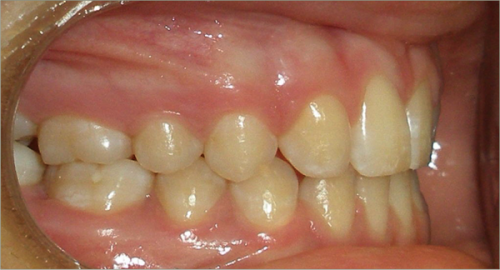

12 year old female:

Diagnosis:

- Missing upper right lateral incisor & lower right cuspid

- Horizontally impacted lower left cuspid

- Peg shaped upper left lateral incisor

Treatment:

- Extraction of impacted lower left cuspid, and peg shaped upper left lateral incisor

- Upper cuspids substituted as laterals

- Full fixed appliances

- 20 months